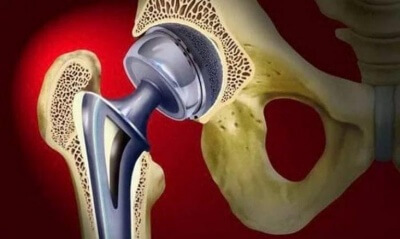

Эндопротезы тазобедреного сустава